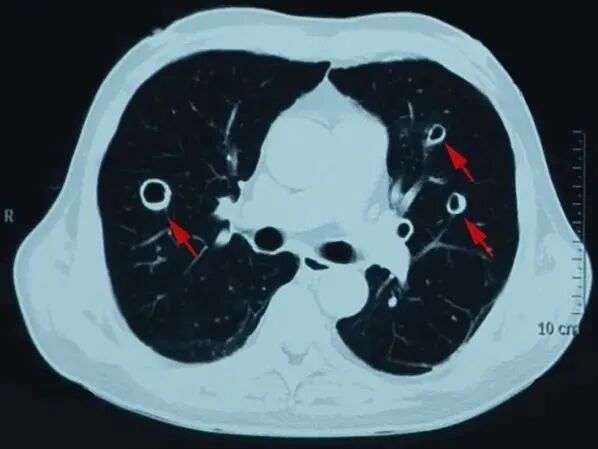

外院CT(图1):

图1:胸腹部CT

胸部CT表现缺乏特异性,可表现为多发结节、晕征、反晕征、空洞等,上叶受累较为多见。本例CT可见多发类似谷物「麦圈」样改变,是首次报道肺毛霉菌病可表现为多发「麦圈征」的病例。「麦圈征」常常由于气道周围肿瘤性或非肿瘤细胞的增殖所致,可见于肺朗格汉斯组织细胞增多症和肺腺癌,偶见于真菌感染、淋巴瘤、类风湿结节和肉芽肿性多血管炎等。肺毛霉菌病亦可以侵犯纵隔或者胸壁,导致慢性纵隔炎和穿透支气管壁、穿透胸壁导致皮下脓肿等。